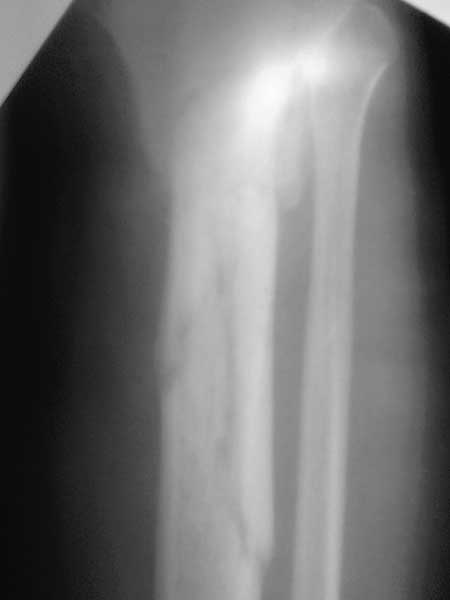

Все таки решились на штифт с антибиотическим покрытием. Выставляю R, в целом считаю неплохо вроде получилось.

После операции у пациента два дня был субфебрилитет 37,4 вечером. Т.к. операция все таки травматичная отделяемое было геморрагическое умеренное- обильное около 2-3 дней, в связи с этим НМГ назначили только на 3день в дозе 0,2*2 р/д п/к =10 дней. Хотя сейчас продвигают идею тромбопрофилактики с первых дней- побоялись кровотечения. Пти около 95-105 в динамике.

После чего п/о гематома начала уменьшаться, отек значительно спал.

Также пациент получал цефтриаксон по 1гр*2 р/д №7 и анальгетики 3-5 дней, эластическое бинтование конечностей со 3 дня постоянно ( не было бинта сразу).

Гипсовой лонгеты не ставили.через недельку разрешили ставить ногу на пятку -не опираясь на конечность.

Швы сняли ок.16 дней после операции- с первичным заживлением, отек незначительный - при выписке на голени.Сосудистых и неврологических нарушений при выписке нет.

При выписке рекомендован прием прадаксы 150 мг 1р/д до 20 дней. Нагружать конечность не разрешили до удаления дистального винта блокиратора до 6 нед. с момента операции.